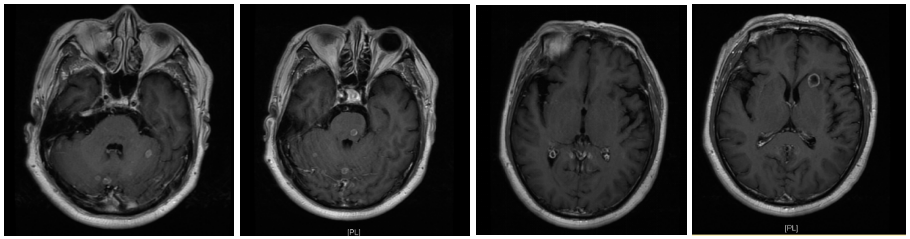

2021-05-31颅脑MRI:脑内多发转移瘤(最大者居于左半卵圆中心,约12×14mm),脑内多发缺血灶。

图4.二线治疗前颅脑MRI结果

2022-03-21颅脑MRI:脑内多发转移瘤复查,较前数量增多,体积增大。

颅脑MRI评估:

对比2022-03-21 MRI脑内多发转移瘤较前减少、减小;双侧大脑白质区及小脑半球、脑干见多发大小不等稍长T1稍长T2信号灶。DWI大部分呈低信号,部分呈环形略高信号,增强后病变未见明显强化,较前减少、减小。

三线治疗疗效评估:颅脑PR、原发灶SD